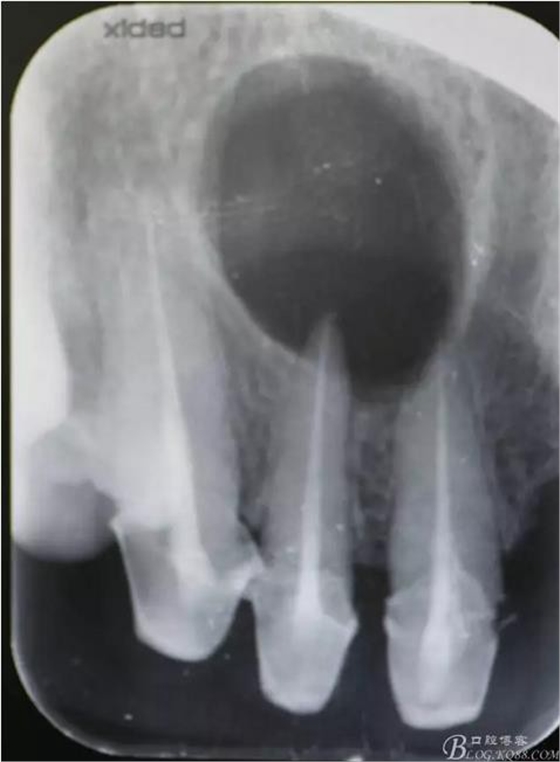

圖2.拆冠、重新根管治療11和12.